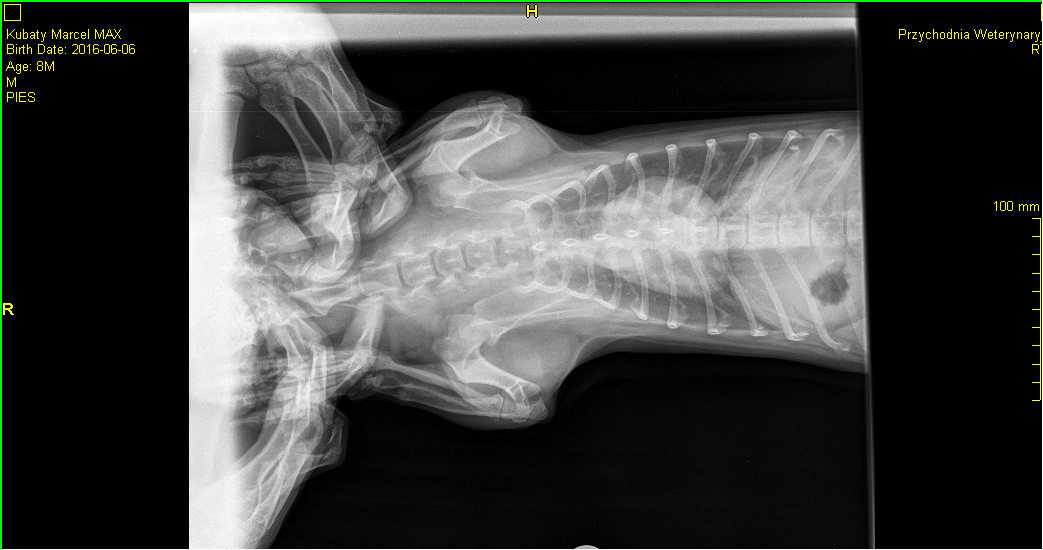

My dog (8-10 months old, small breed , similar to dachschund) had a problem with breatching - he had a dyspnoea attacks, he was exhaling with a lot of effort. he had rhinoscopy and was diagnosed with some kind of acute inflammation of soft palate. Now he is taking Prednisone 1mg/kg and the attacks are gone, but when i try to go down with the dosage, the attacks come back. Is there something that can cause such a state? I'm not sure whether Prednisone will eliminate the cause.... Greetings

Some dogs will have an elongated soft palate that can become inflamed, and prednisone helps reduce inflammation. Dachshunds are also more likely to develop a disease called lymphocytic-plasmacytic rhinitis that causes chronic nasal inflammation. This disease is usually diagnosed by taking biopsy samples during a rhinoscopy. In either case, the prednisone would probably not completely eliminate the disease and some kind of medication might be needed long term. I would recommend discussing treatment options with your veterinarian. I think his chest x-rays look normal for his breed.